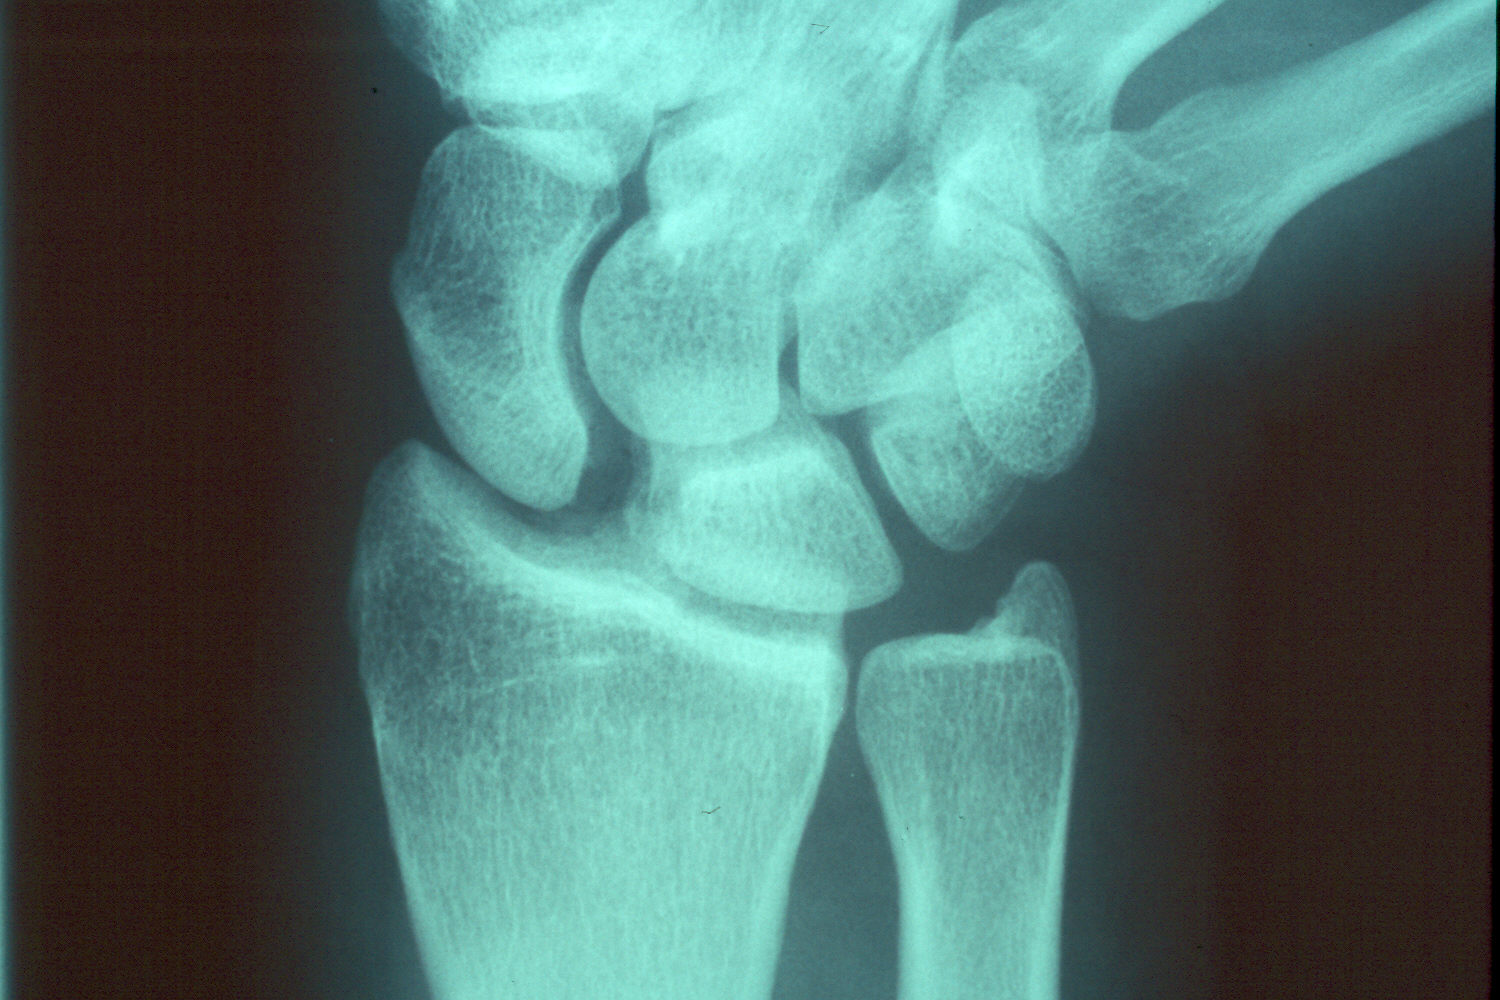

In this case, a significant length of ulna was removed. A longitudinal groove was made in the ulna and marked with ink prior to oblique osteotomy to aid confirmation of alignment for fixation.

As might be expected, the ends of the ulna could not be easily brought together.repositioning of the distal ulna segment required an extensive exposure as detailed in

this other case.